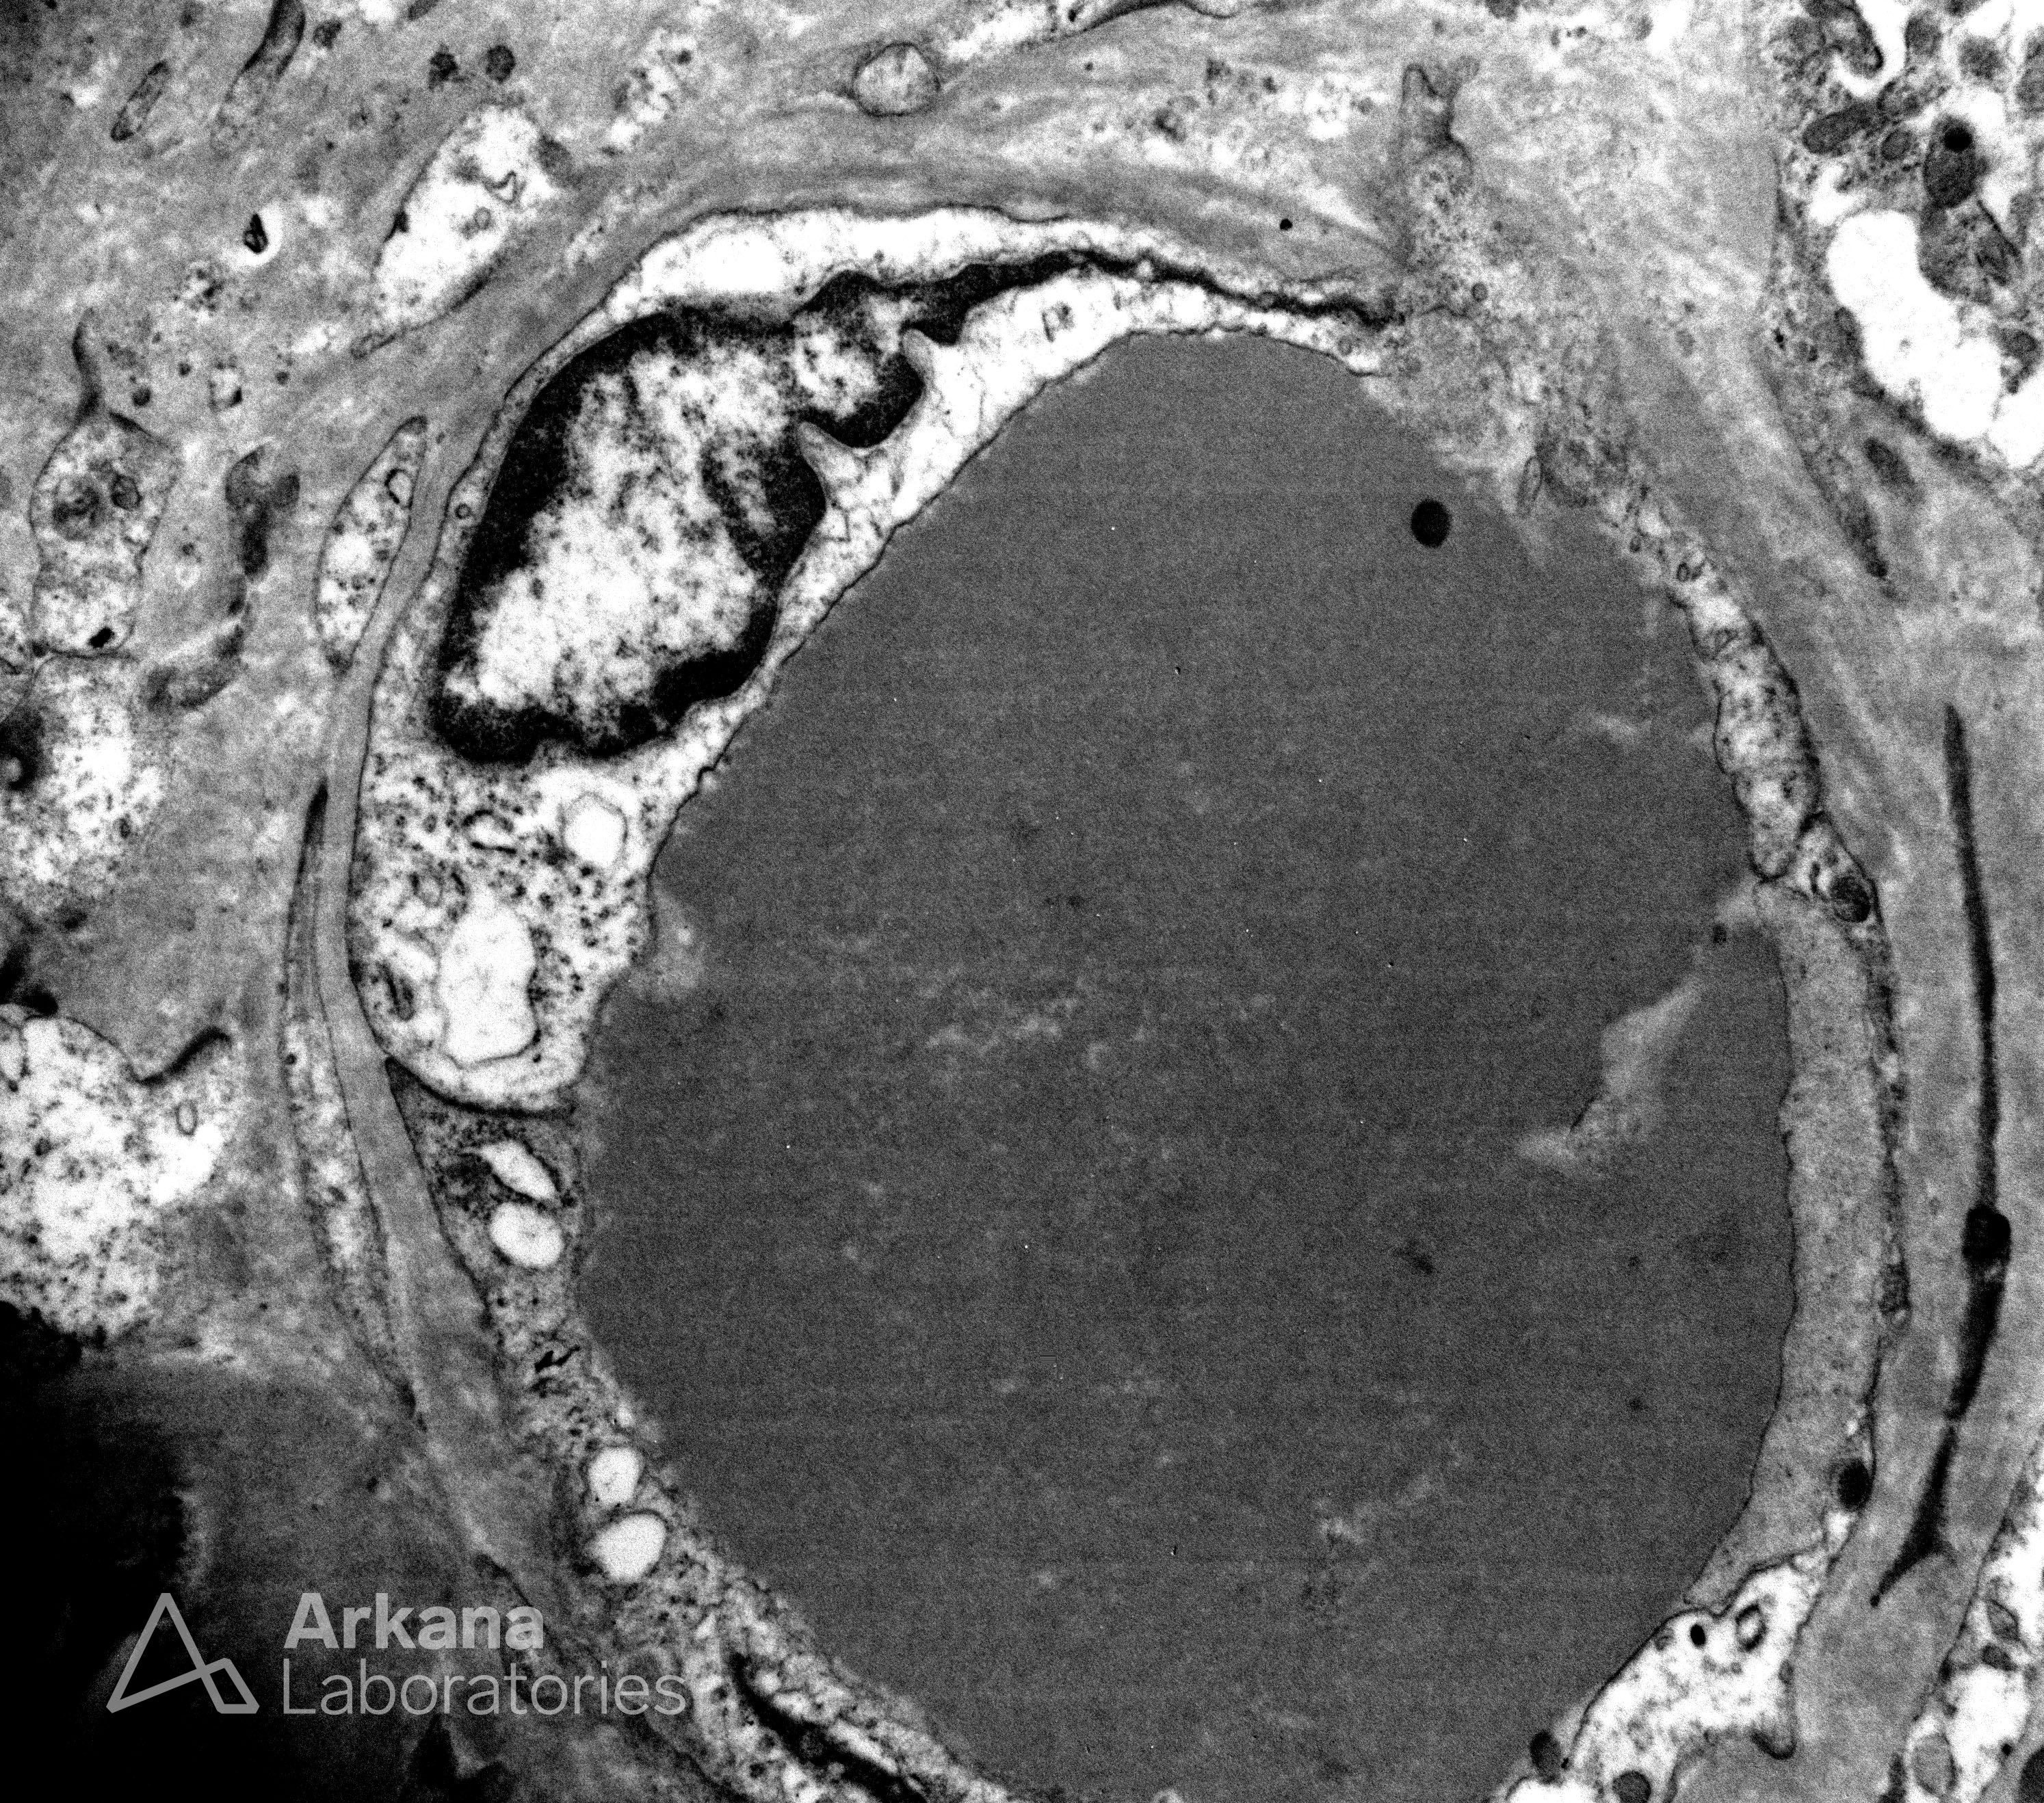

Hylaine Thrombus with Vague Substructure on EM